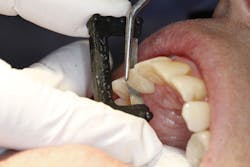

Figure 2: Proximal contact adjustment is simpler than ever and vital to the care patients expect.

When restoring interproximal relief-the natural, comfortable, passive contact or microscopic clearance between teeth-there is fortunately an easier and far more accurate way to adjust proximal contacts. Using a thin (0.06 mm or less), single-handed, single-sided diamond strip, we can perform necessary adjustments intraorally and without articulating films and rotary instruments. After placing the crown on the prepared tooth and noting the contact intensity and marginal fit, the diamond strip is simply passed buccolingually through both the mesial and distal interproximal spaces until equal light resistance is felt (figure 2). This ensures complete marginal seating and a far more satisfying patient experience.